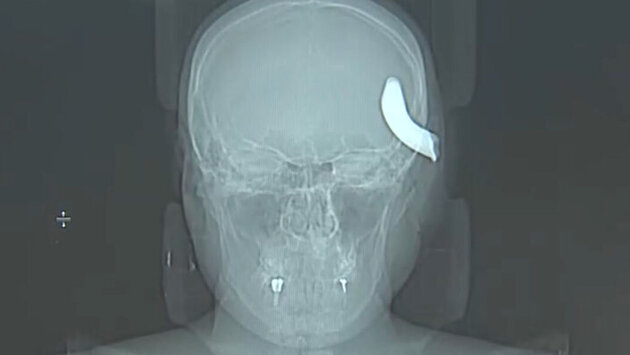

В Петербурге нейрохирурги извлекли из черепа молодого мужчины металлический крюк от буксировочного троса

Несчастный случай произошел в Приморском районе в апреле, когда мужчина решил помочь другу с буксировкой автомобиля. Когда машину тянули, зацепив тросом, крюк на нем размером 6х4 см не выдержал, оторвался и с силой отлетел прямо в голову Никиты. Так, с металлическим крюком в голове, пострадавшего и доставили во второе нейрохирургическое отделение больницы.

Хирурги в экстренном порядке отправили пострадавшего на операционный стол, провели ему декомпрессивную трепанацию черепа и удалили металлический фрагмент. Операция длилась три часа.